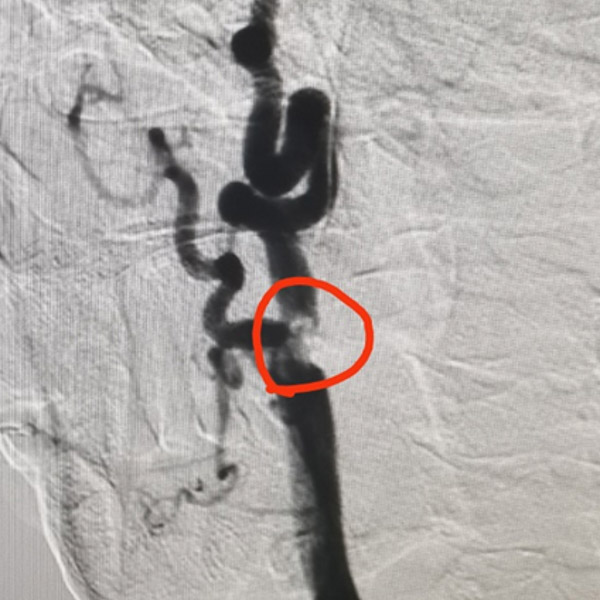

徐阿婆的家屬意識(shí)到了問題的嚴(yán)重性,立即將徐阿婆送至我院卒中中心,卒中中心專家霍鑫博士、高文博士查看病情后,一致認(rèn)為患者因頸動(dòng)脈狹窄較重,分叉位置較高,且遠(yuǎn)端血管迂曲明確,無法行支架植入,建議行頸動(dòng)脈內(nèi)膜剝脫術(shù)。

經(jīng)過充分的準(zhǔn)備,多學(xué)科共同協(xié)作,為徐阿婆行頸動(dòng)脈內(nèi)膜剝脫術(shù),最終順利切除一塊長(zhǎng)約2cm的斑塊。術(shù)后復(fù)查頸動(dòng)脈CTA,顯示右側(cè)頸內(nèi)動(dòng)脈重度狹窄恢復(fù)正常。